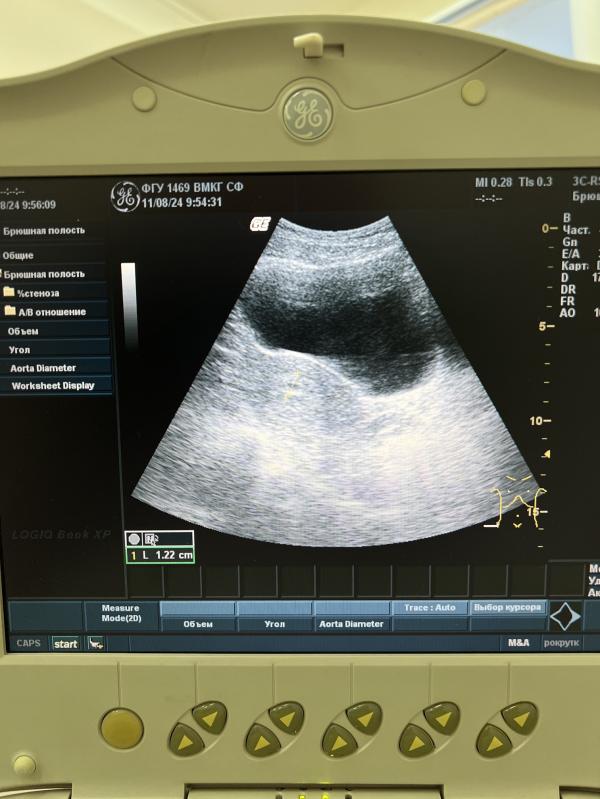

В пятницу была на узи. Правда переживаний после него только прибавилось🙈 аппарат здесь старый, вообще не предназначен для гинекологического узи! Датчик только поверху! На полный мочевой, чтоб матку видно было) и гинеколог, которая только вышла с декрета)) намерила она мне вообщем 10-12 мм ПЯ, хотя во вторник еще на узи не могли поймать ПЯ, и ставили размер около 4 мм!!!